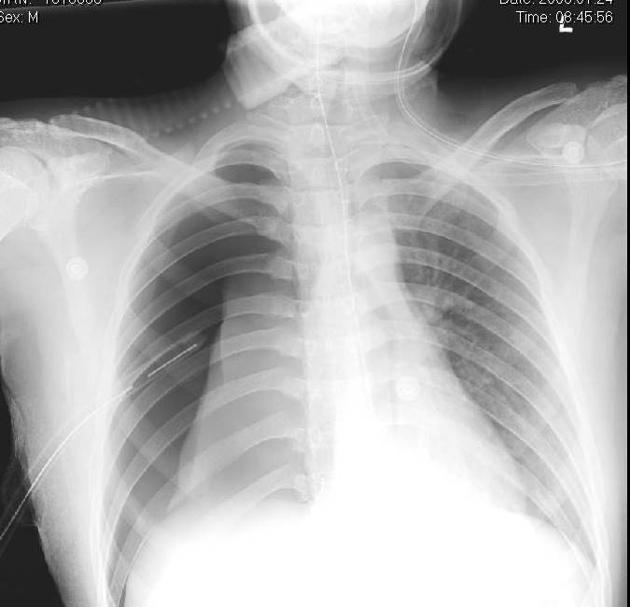

Describe the abnormality demonstrated.

Right-sided pneumothorax (loss of lung markings)